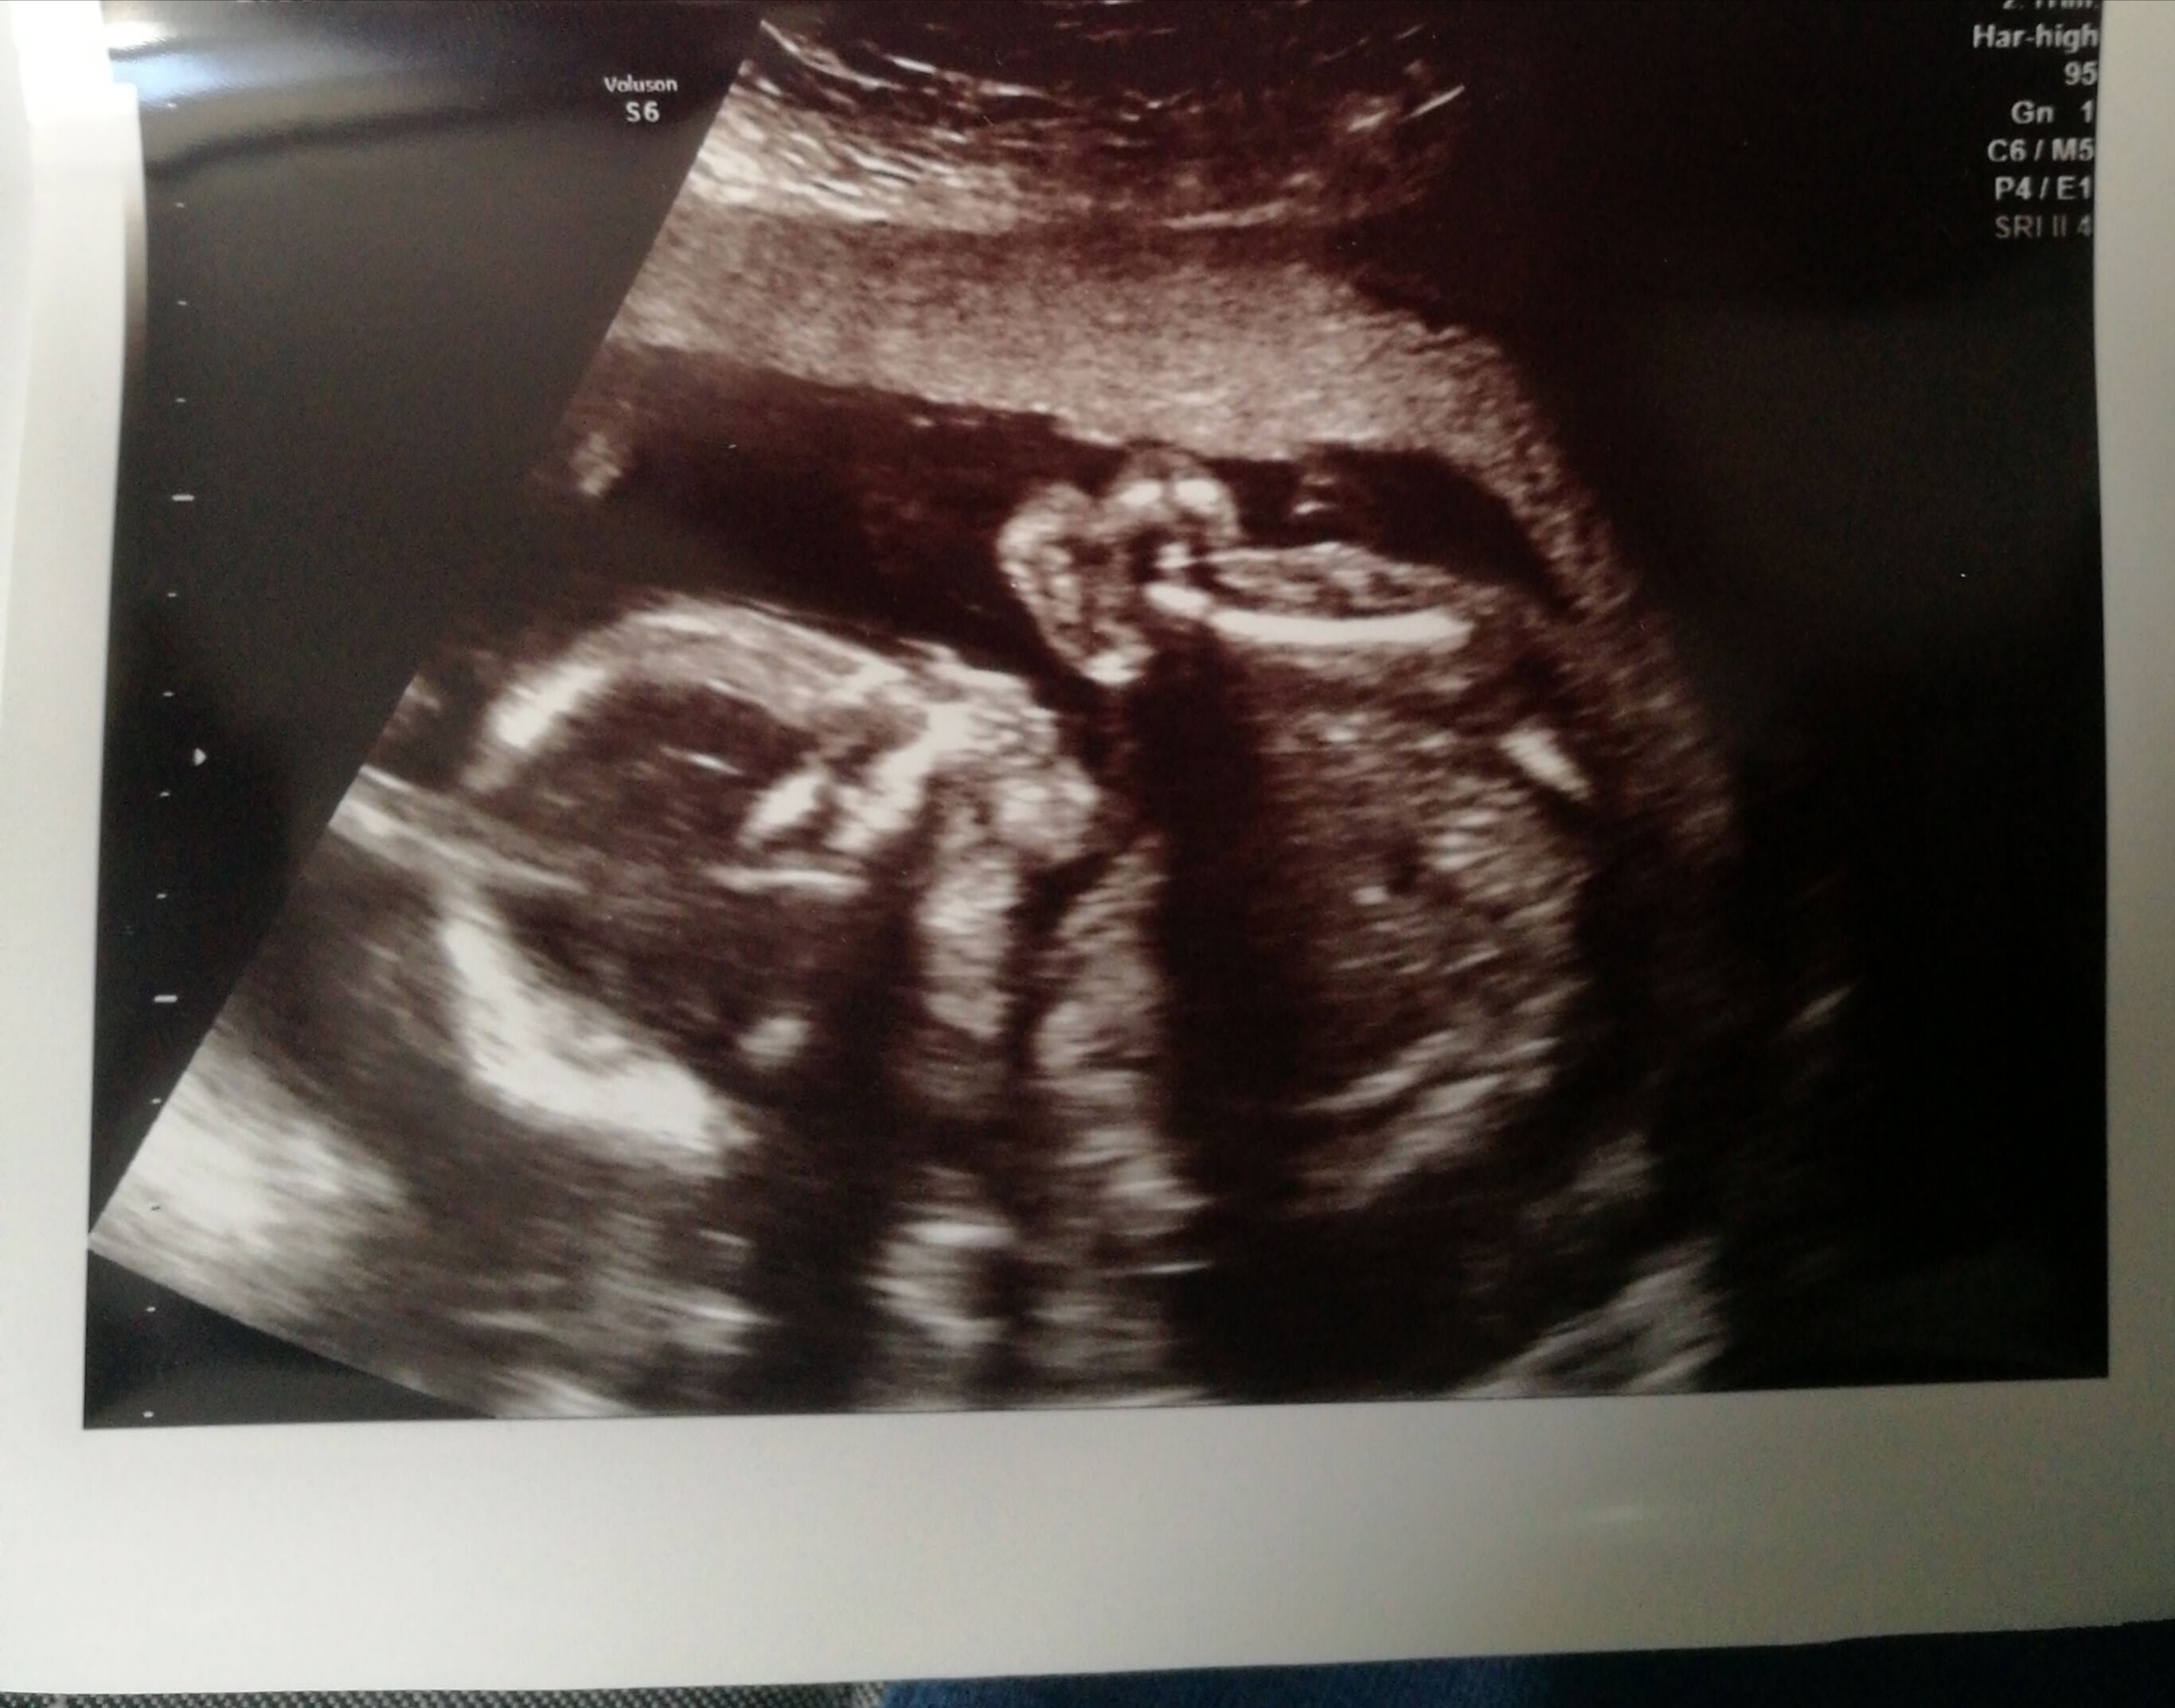

Gratulacje,który to tydzień?Forumowe ciocie, mam przyjemność poinformować, ze na połówkowych wszystko super ❤ maluch ma 409 gram i wszystkie narządy na swoim miejscu ❤❤❤